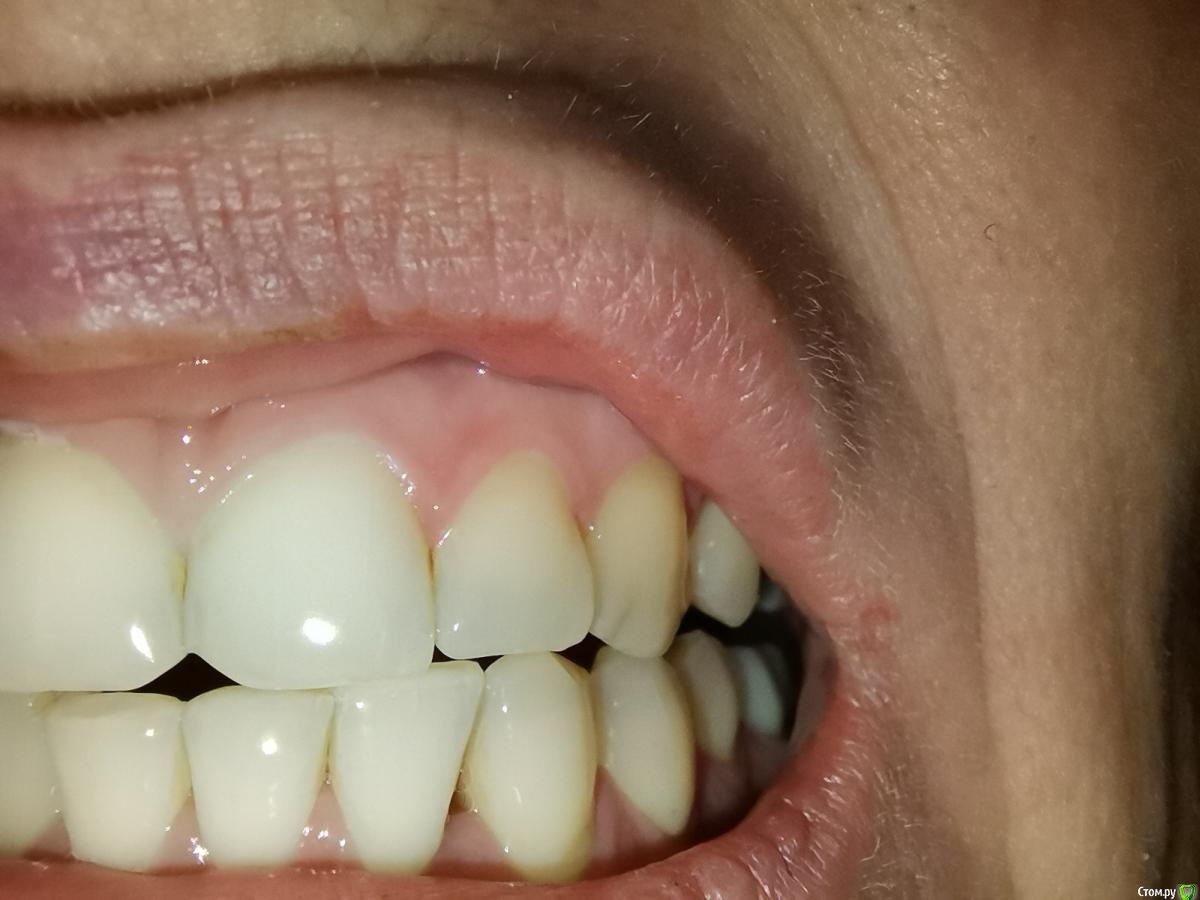

Прошу совета по поводу своих проблем с деснами. Они у меня не кровоточат, не болят, но между жевательными зубами у меня исчезли десневые сосочки и если зубы пошатать, то они как бы двигаются (если шатать от неба к губам то не шатается, если между зубами, то как бы отходят друг от друга и слышится треск неприятный). Также стали исчезать сосочки между центральным и верхним зубами и двойками - появились небольшие дырочки

Сделала к-т для следующего врача и сделала фото с к-т. Можете посмотреть, тяжёлый ли пародонтит во всей челюсти и особенно около левых верхних зубов с 4 по 7. Как лечиться и куда бежать?

У меня между нижним зубами с 4 по 4 и верхним между 1 и 2 начали появляться щели, межзубный сосчек исчезает какими то очень быстрыми темпами - 2 месяца назад все было хорошо. Может подскажите с чем это может быть связано? Может быть с нижним 8, которые удаляла как раз в октябре это как то может быть связано. Боюсь эти сосчки исчезнут навсегда (